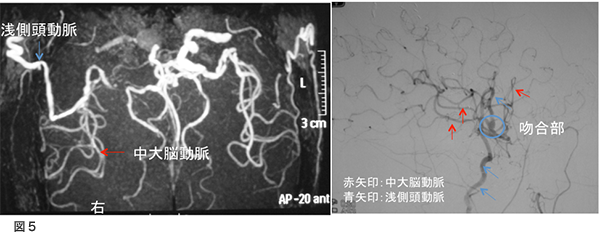

脳血流検査(CT perfusion)図6

術後検査として造影剤を使用したCTで血流評価をしました。この結果、脳血流量の左右差はほとんど消失しています。